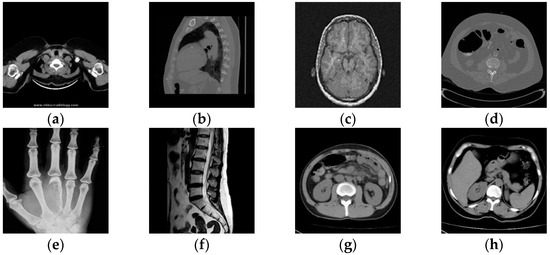

3.2.2. Data Set Creation

The medical image data selected for this paper comes from the Medical Imaging Park and American Research Institute, Inc., which contains tens of thousands of medical images. In this paper, we selected 125 medical images in each of the five major categories of brain, pelvis, bone and muscle, colon, and chest from the website as dataset 1, and encrypted these 125 medical images to obtain 125 encrypted medical images as dataset 2. Some of these 250 images are shown in Figure 5. Data sets 1 and 2 are completely disrupted, respectively, and then divided into three parts in the ratio of 3:1:1: the training set, validation set, and test set. In order to improve the robustness of the network in extracting features, in this paper, the training set and the validation set are enhanced with the data separately, as shown in Table 1. Thus, we obtained 12,850 images as the total dataset for this training. Because the input size of the DarkNet53 convolutional neural network is 2,562,563, all medical images are resized to 2,562,563 here. For the production of dataset labels, this paper first performs DCT on the images of the training and validation sets and then selects the 128-bit feature vectors of the low-frequency part as labels.

Figure 5.

Two original images and corresponding encrypted images for each type of image. Brain image (a); abdominal pelvis image (b); bone muscle image (c); colon image (d); and chest image (e).